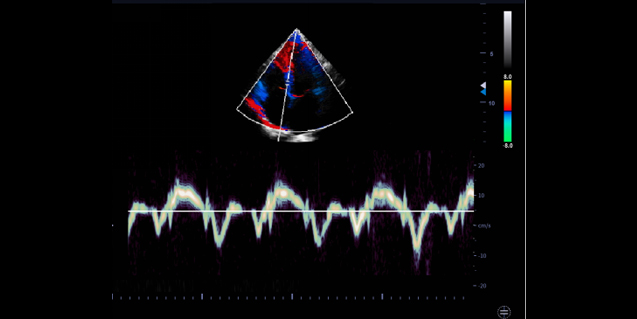

临床图像